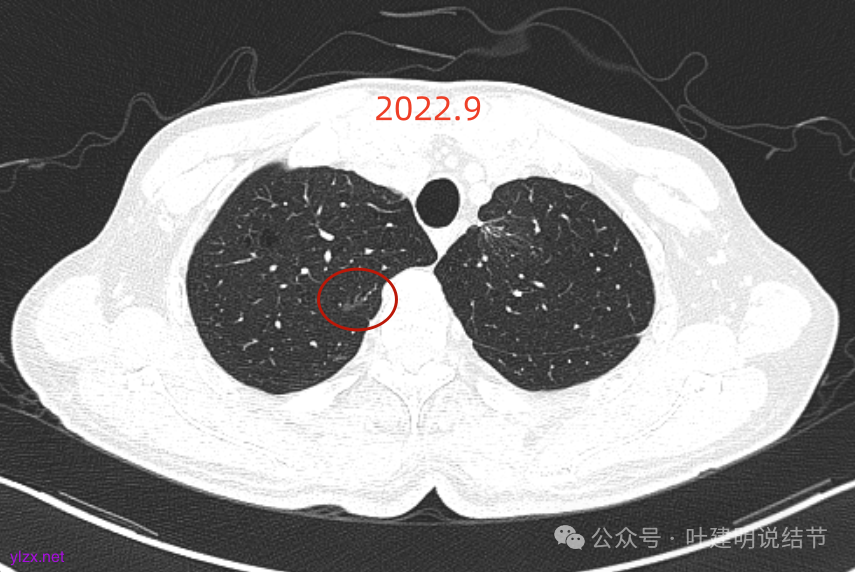

再看2022年9月的:

右上病灶此层面偏长条,密度较低。

左上已经手术。

左上另有一处磨玻璃结节,由于手术后结构变化,此灶是术前哪处感觉不太好对比。